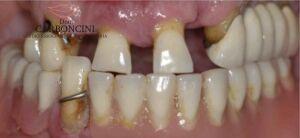

Riabilitazione protesica su impianti in paziente con malattia parodontale

Il paziente aveva perso la maggior parte dei denti a causa della malattia parodontale , e stava perdendo i restanti per lo stesso motivo. Dopo le estrazioni furono inseriti 4 impianti nell’arcata superiore e 4 nell’arcata inferiore seguendo il protocollo del carico immediato.

Restauro protesico finale eseguito con 8 impianti e 22 corone in oroceramica.

DOPO